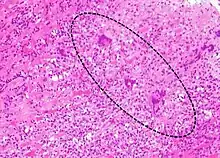

IGCM frequently leads to death with a high rate of about 70% in first year. A patient with IGCM typically presents with symptoms of heart failure, although some may present initially with ventricular arrhythmia or heart block. Median age from the time the disease is diagnosed to the time of death is approximately 6 months. 90% of patients are either deceased by the end of 1 year or have received a heart transplant. Diagnosis is made by endomyocardial biopsy during heart catheterization. Biopsy shows multinucleated giant cells and thus the name. While previously cases universally required heart transplantation, recent studies show that two-thirds of patients can survive past one year with high doses of immunosuppressants such as prednisone and cyclosporine. The transplanted heart has a high chance of disease recurrence. Compared to lymphocytic (presumed viral) myocarditis, giant cell myocarditis is much more severe with much more rapid progression.